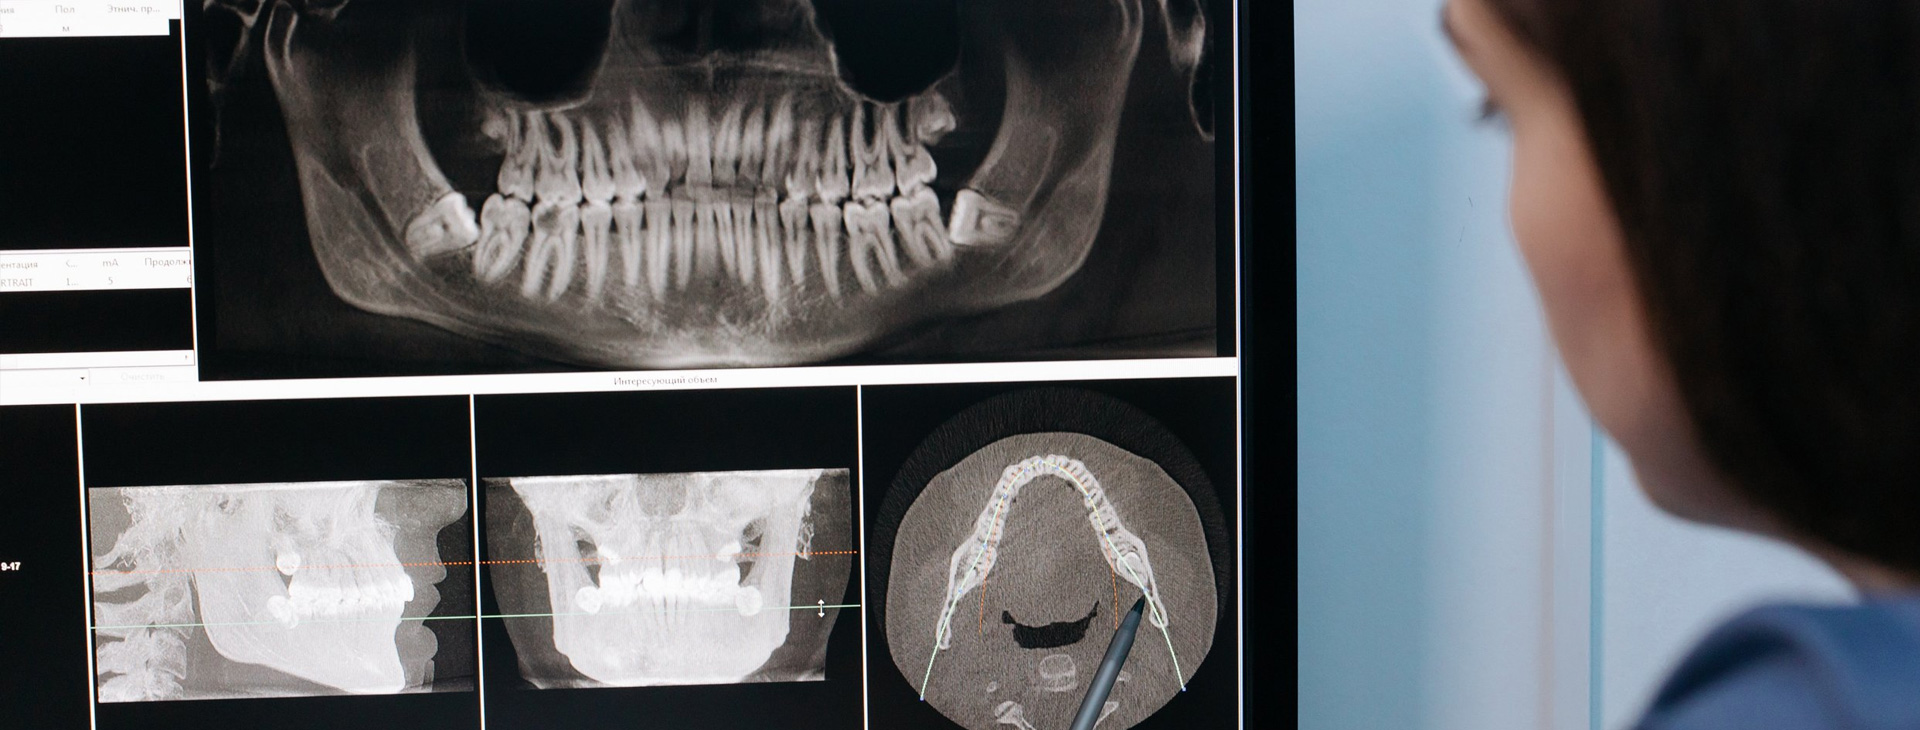

Rayos X Dentales en Puebla

Equipo especializado, tecnología 100% digital avanzada

Las radiografías dentales digitales son imágenes de los dientes y la boca que se toman utilizando un sensor digital en lugar de una película. Las radiografías digitales ofrecen una serie de ventajas sobre las radiografías tradicionales, obteniendo imágenes más nitidas y precisas, lo que ayuda a los especialistas a regenerar diagnósticos mucho más precisos y específicos para cada paciente. De la misma manera las radiografías dentales digitales se pueden utilizar para planificar el tratamiento dental, como la colocación de coronas, puentes o implantes.

Rayos X Digitales

Equipo especializado con mayor nitidez y contraste permitiendo apreciar mejor los detalles y densidades.